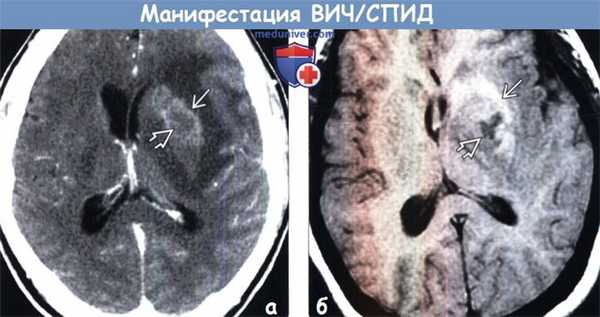

Диагностика связанных с ВИЧ/СПИД инфекций, опухолей головного мозга по КТ, МРТ

(а) КТ с контрастированием, аксиальный срез: у ВИЧ-положительного пациента с припухлостью кожи волосистой части головы определяется объемное образование мягких тканей с инфильтративным типом роста, вызывающее утолщение кожи волосистой части головы левой лобной области. При биопсии была обнаружена саркома Капоши. Саркома Капоши относится к группе СПИД-определяющих опухолей (СОО).

2. КТ признаки манифестации ВИЧ/СПИД:

(а) КТ с контрастированием: у ВИЧ(+) пациента с одиночным объемным образованием, расположенным в области базальных ганглиев, вокруг зоны его центрального некроза определяется слабо заметное накопление контрастного вещества.

(б) МРТ, Т1-ВИ, аксиальный срез: у этого же пациента вокруг некротического ядра определяется повышение интенсивности сигнала вследствие подострого кровоизлияния. При лимфоме ЦНС редко наблюдаются кровоизлияния или некротические изменения, исключение составляют иммунокомпрометированные пациенты.